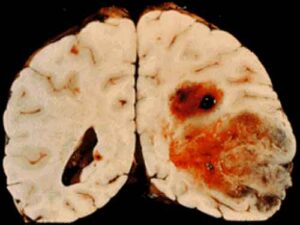

Ink4a-ArfLoss Cooperates with KRas Activation in Astrocytes and Neural Progenitors to Generate Glioblastomas of Various Morphologies resulting tumors were nestin positive and resembled a spectrum of glioma morphologies ranging in astrocytic character depending on cell-of-origin ... Content Retrieval

Combined expression of activated forms of both KRas and Akt in glial progenitor cells. To determine the reliance of these tumors on continued KRas signaling in vivo, progresses from a low-grade glioma to a high-grade glioma through the acquisition of additional genetic alterations (5). Primary ... Read More

Using PDGF- and KRAS-driven murine models of gliomagenesis, we show that high Id1 expression (Id1high) Since the discovery of glioma cells with properties reminiscent of neural stem cells, including the capacity to self-renew, there has been a great deal of interest in elucidating their ... Fetch Doc

Cell Reports Supplemental Information Ets Factors Regulate Neural Stem Cell Depletion and Gliogenesis in Ras Pathway Glioma Joshua J. Breunig, Rachelle Levy, C. Danielle Antonuk, RTK/Kras tumorigenesis, examples from WT Hras and Errb2 overexpression, and pathological findings in Erbb2 V664E ... Retrieve Doc